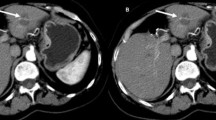

Post-CA cryolesion patterns of a biopsy-proven well-differentiated HCC. a–c Images obtained 1 day before the procedure. a On the B-mode, the lesion measured 3 cm at its longest diameter and appeared hypoechoic; its volume was estimated at 5 ml. b On CEUS 25 s after IV contrast-medium injection, the lesion (arrows) appeared rather hypovascularised with heterogeneous enhancement. c At 110 s after IV injection and later (not shown), the lesion was not clearly washed out. d–f T1 images obtained on D1 post-procedure. d On B-mode, a hypoechoic area measuring 4.3 cm at its longest diameter is seen (between calipers). e The CEUS image obtained 26 s after IV injection shows the persistence of numerous remaining enhancing vessels penetrating into the whole treated area (arrows) leading to classification of the margins as “undefined”. In addition, a thick enhancing rim (arrowheads) was also clearly visible. f At 110 s after IV injection, the treated area appeared more poorly vascularised than before cryoablation; its volume was calculated at 16 ml. g–i T3 images obtained at week 12 post-procedure. g On B-mode a hypoechoic area (between calipers) measuring 2.8 cm at its longest diameter is seen. h The CEUS image obtained 40 s after IV injection still showed undefined margins with persistence of numerous remaining enhancing vessels penetrating into the treated area (arrows) except a small central zone. The enhancing rim was no longer visible. i At 119 s after IV injection, the treated area appeared better vascularised than at T1; its volume was estimated at 7 ml. j–l T4 images obtained at month 6 post-ablation. j The CEUS image obtained 26 s after IV injection still shows undefined margins with persistent enhancing vessels penetrating into the whole treated area (arrows). k That observation led to a percutaneous CEUS-guided biopsy of the treated area to rule out incomplete treatment (the arrowhead shows the biopsy needle). l Histological examination found a hypervascular fibrosis without any tumour cells. The patient was followed for 2 additional years without recurrence

CA-induced thermal damage is the consequence of rapid freezing of tissues [26–29]. Close to the cryoprobe, the temperature rapidly achieves –190 °C, causing intra- and extracellular ice formation. Subsequent cell-membrane rupture during thawing and dehydration results in cell death. Further from the probe, where the temperature decreases more slowly, ice forms and propagates preferentially along the vascular system, within venules and arterioles, because cell walls impede intracellular ice crystal formation [27]. The resulting short-term hypoxia contributes to the death of surviving cells. However, it has been shown that canine large blood vessels were less sensitive to freezing injury than smaller vessels and bile ducts [30]. Consequently, at the periphery of the treated area, more small capillaries are expected to be destroyed than larger vessels, creating a blurred transition zone. And like for RF lesions, an inflammatory reaction with granulation tissue occurs outside and probably overlapping the transition zone, as described during histopathological analysis of cryolesions induced in rabbit livers 7 days after CA [21]. In that study, cryolesions, 15 mm in diameter, exhibited central coagulation necrosis with peripheral hepatic arterial and portal venous branches penetrating as much as 6 mm into the cryolesions, blood lakes similar to peliosis lesions and a peripheral 1–5-mm-thick rim of granulation tissue and inflammation [21]. Those histopathological features clearly correspond to our CEUS findings. Indeed, cryolesion margins were significantly less well defined at T1 than for RF lesions. Moreover, the enhancing rim was significantly thicker and more frequent around cryolesions than around RF lesions. On one hand, it is important to know that numerous peripheral small vessels that penetrate deep into a cryoablated area can persist after successful treatment. On the other hand, the persistence in 67 % (8/12) of the patients of such vascularisation, associated with the presence of a thick enhancing rim around this area, can preclude the identification of residual tumour, particularly a few days after the procedure.